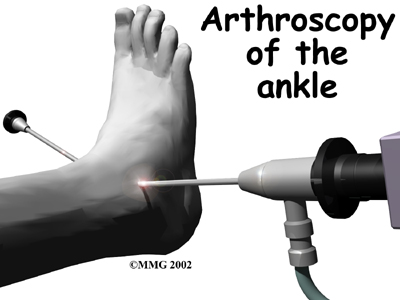

Your ankle will be bandaged with a well-padded dressing and a splint for support after surgery. Most patients are instructed not to place weight on their foot for a period of time after surgery. After arthroscopy, this period typically lasts about one week. Although recovery time is not the same for everybody, after ankle joint replacement, most patients are usually advised to avoid placing weight on their foot for up to 12 weeks.